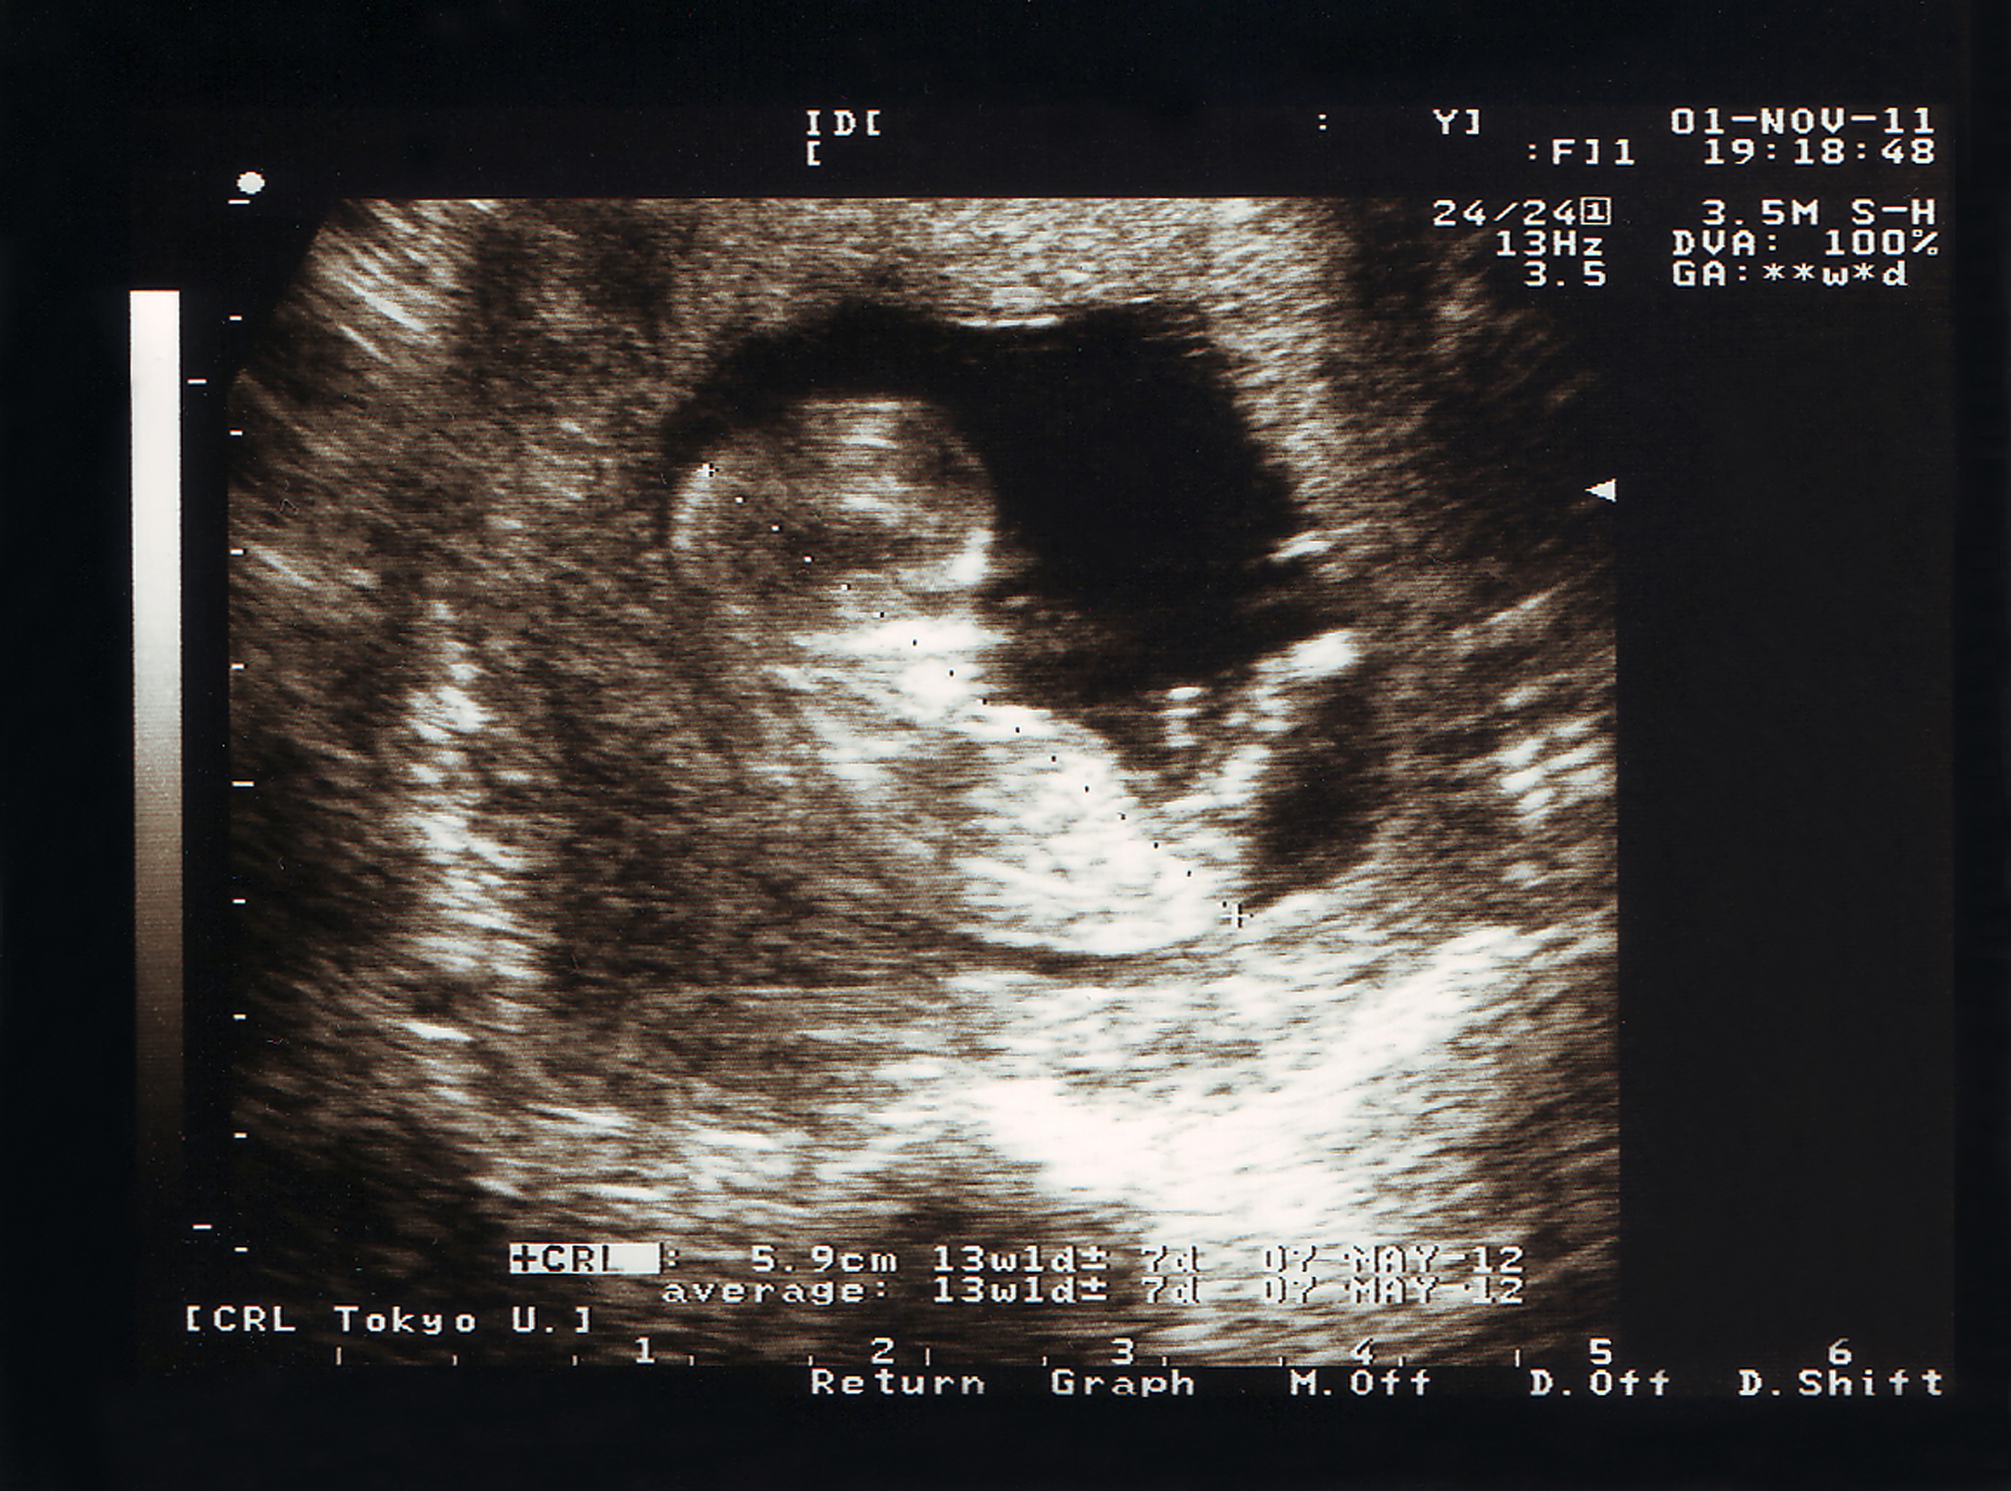

En los embarazos múltiples, como mellizos o gemelos, ambos embriones se conciben al mismo tiempo. En la superfetación, en cambio, los fetos tienen edades gestacionales diferentes, a veces separadas por semanas.

Esto puede generar confusión en los controles prenatales, ya que uno de los bebés puede verse más pequeño, llevando al médico a sospechar problemas de crecimiento cuando en realidad se concibió días o semanas después.